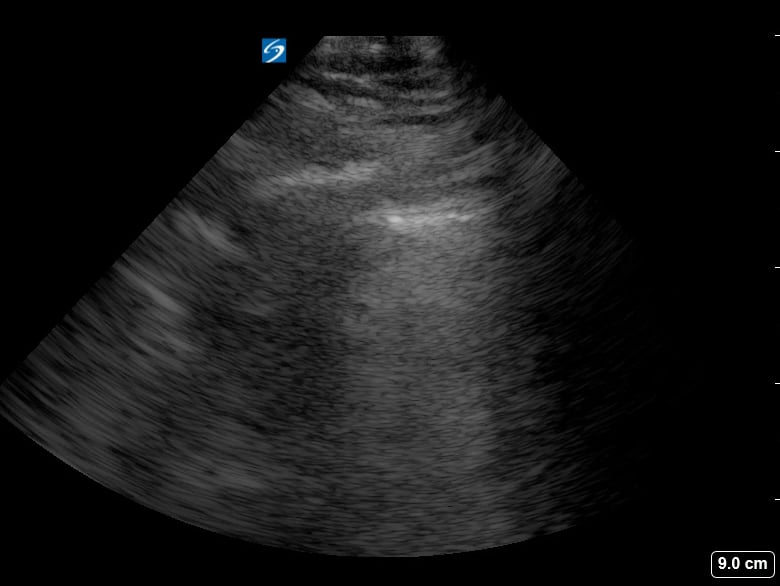

Subpleural consolidation in lung ultrasound refers to an area of lung tissue solidification located directly beneath the pleura, the lining of the lungs. This finding is critical in medical imaging, often indicating inflammatory processes like pneumonia, atelectasis, or pulmonary infarct. Ultrasound excels in visualizing these superficial lung changes due to its high resolution in the near field, making it a valuable tool for bedside assessment and monitoring of lung pathologies.

Identifying subpleural consolidation is crucial for accurate diagnosis and patient management. Its presence can guide clinicians in differentiating various lung conditions, especially in emergency and critical care settings where rapid assessment is vital. Ultrasound’s non-ionizing nature and portability further enhance its utility for repeated evaluations and monitoring of lung disease progression.